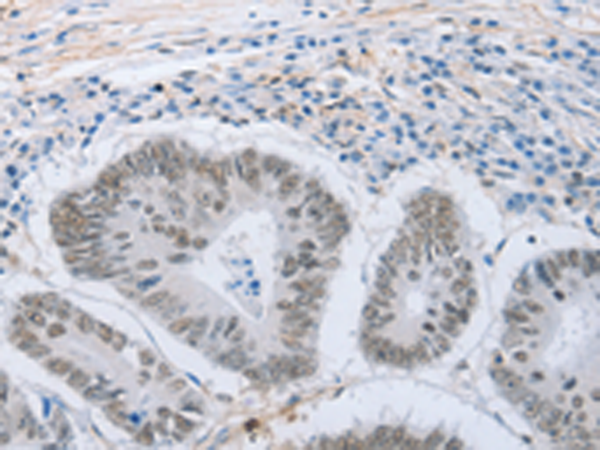

分类: 科研抗体货号: P04417别名: PD1, PD-1, CD279, SLEB2, hPD-1, hPD-l应用: IHC反应种属: Human